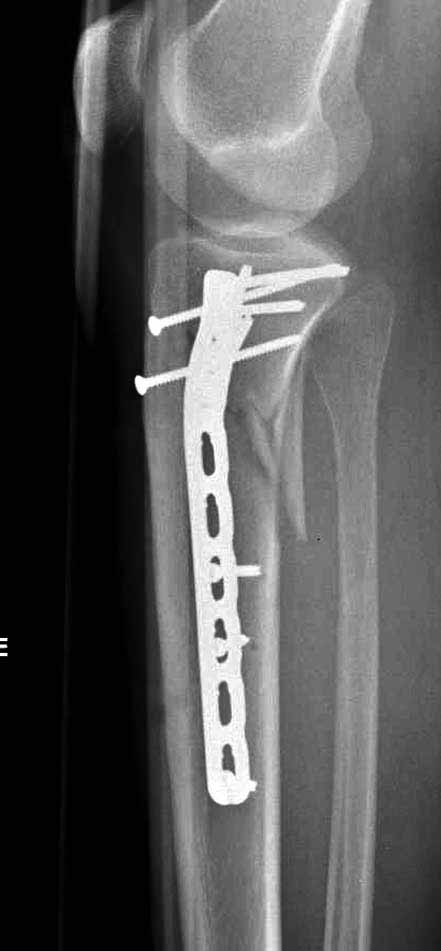

В приложении этапы фиксации пластиной Synthes для плеча при переломе медиального мыщелка.

Имя     : 1 medial column tibial plateau.JPG

Тип     : image/jpg